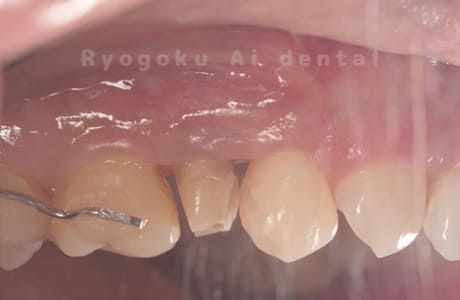

Case04

-

- 原因

- 重度カリエス、C3急化Pul

- 治療期間

- 約6ヶ月

- 治療内容

- 部分矯正、クラウンレングスニング、セラミッククラウン

- 治療費用

- 約350,000円

他院での説明で抜歯した後にインプラント治療を提案された患者さんです。虫歯が大きく、被せるための歯の長さが足りないため、埋まっている歯牙を引っ張り上げ、セラミックで被せたケースです。歯牙の状態も良好で、問題なく経過しています。